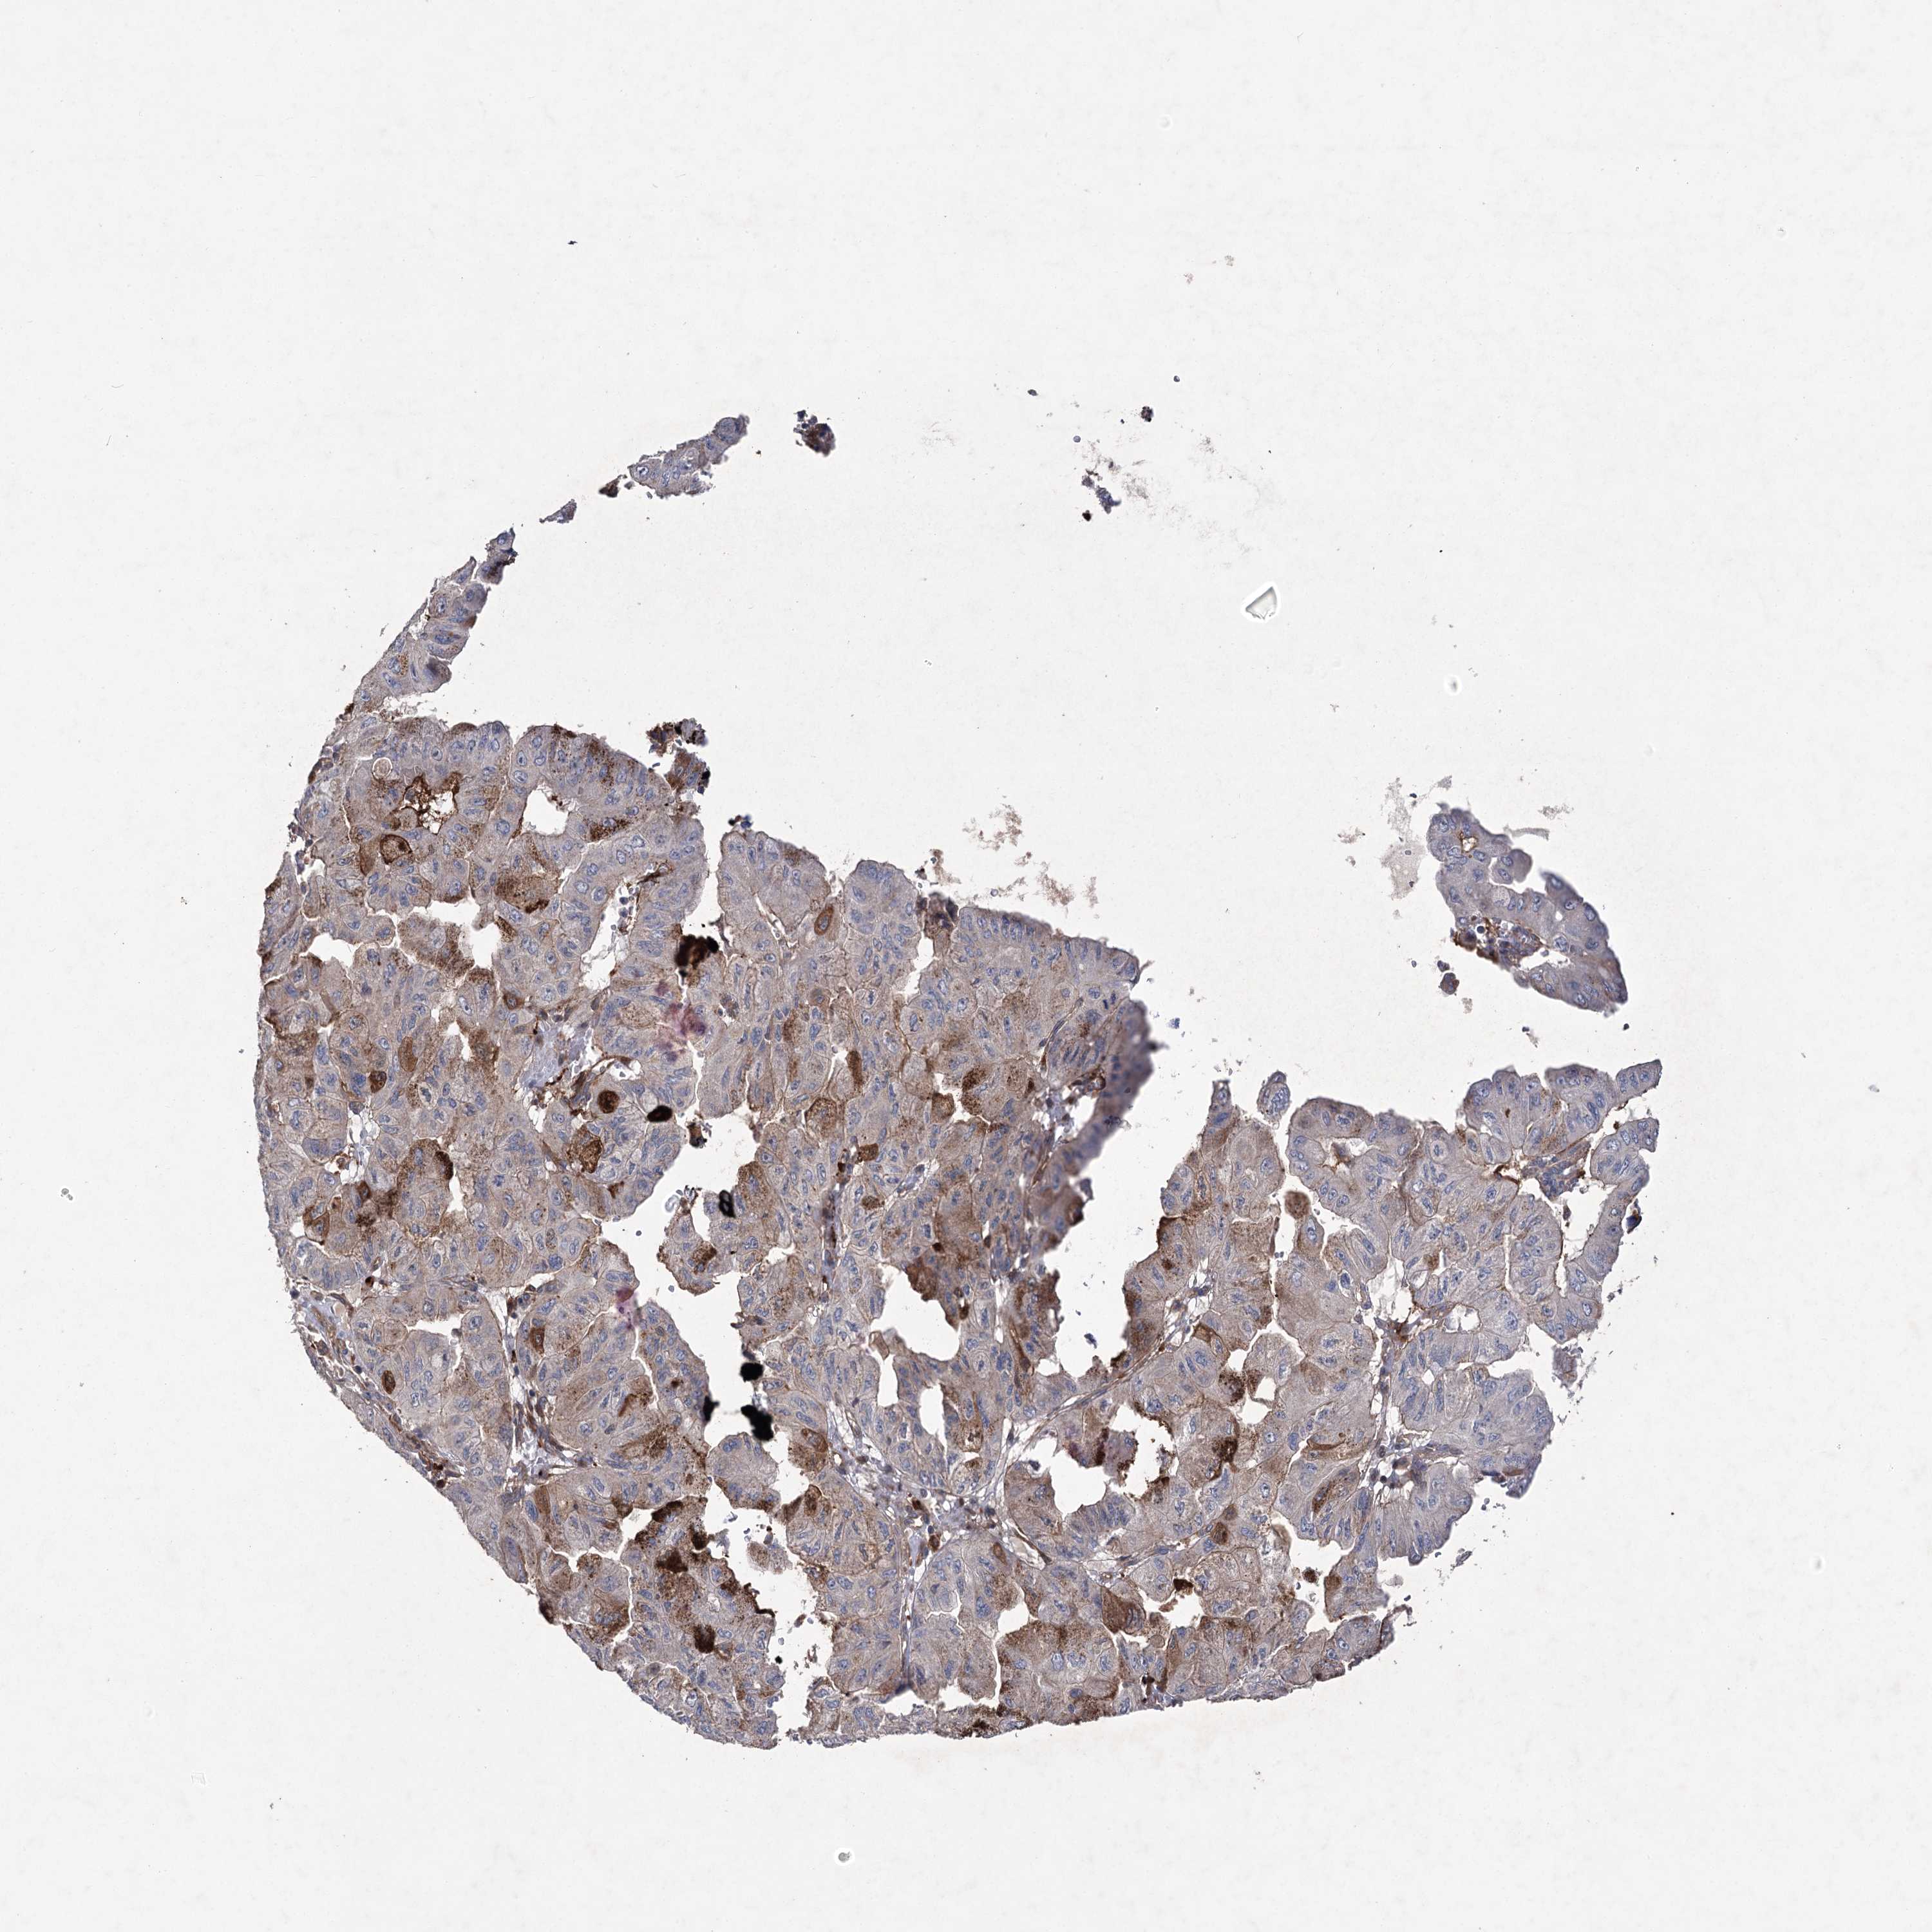

PANCREATIC CANCER - Protein expressioni

A mouse-over function shows sample information and annotation data. Click on an image to view it in a full screen mode. Samples can be filtered based on level of antibody staining by selecting one or several of the following categories: high, medium, low and not detected. The assay and annotation is described here.

Note that samples used for immunohistochemistry by the Human Protein Atlas do not correspond to samples in the TCGA dataset.

Antibody stainingi

Antibody staining in the annotated cell types in the current human tissue is reported as not detected, low, medium, or high, based on conventional immunohistochemistry profiling in selected tissues. This score is based on the combination of the staining intensity and fraction of stained cells.

Each image is clickable and will lead to virtual microscopy that enables deeper exploration of all samples and also displays staining intensity scores, fraction scores and subcellular localization as well as patient and tissue information for each sample.

Antibody HPA038504

Staining

High

Medium

Low

Not detected

Intensity

Strong

Moderate

Weak

Negative

Quantity

>75%

75%-25%

<25%

None

Location

Nuclear

Cytoplasmic/membranous

Cytoplasmic/membranous,nuclear

Adenocarcinoma, NOS